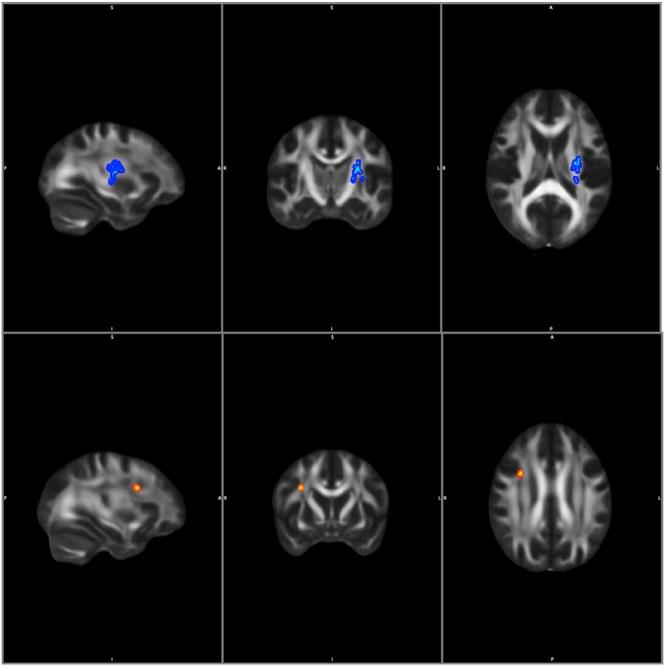

Formerly white matter abnormalities in a mixed group of migraine patients with and without aura were shown. Here, we aimed to explore white matter alterations in a homogeneous group of migraineurs with aura and to delineate possible relationships between white matter changes and clinical variables. Eighteen patients with aura, 25 migraine patients without aura and 28 controls were scanned on a 1.5T MRI scanner. Diffusivity parameters of the white matter were estimated and compared between patients' groups and controls using whole-brain tract-based spatial statistics. Decreased radial diffusivity ( < 0.036) was found bilaterally in the parieto-occipital white matter, the corpus callosum, and the cingular white matter of migraine with aura (MwA) patients compared to controls. Migraine without aura (MwoA) patients showed no alteration compared to controls. MwA compared to MwoA showed increased fractional anisotropy ( < 0.048) in the left parieto-occipital white matter. In MwA a negative correlation was found between axial diffusivity and disease duration in the left superior longitudinal fascicle (left parieto-occipital region) and in the left corticospinal tract ( < 0.036) and with the number of the attacks in the right superior longitudinal fascicle ( < 0.048). We showed for the first time that there are white matter microstructural differences between these two subgroups of migraine and hence it is important to handle the two groups separately in further researches. We propose that degenerative and maladaptive plastic changes coexist in the disease and the diffusion profile is a result of these processes.

既往研究显示,有先兆和无先兆的混合偏头痛患者组均存在白质异常。在此,我们旨在探讨有先兆偏头痛患者同质组中的白质改变,并描绘白质变化与临床变量之间的可能关系。18名有先兆患者、25名无先兆偏头痛患者和28名对照者接受了1.5T磁共振成像扫描仪扫描。使用基于全脑纤维束的空间统计学方法,估计并比较患者组与对照组之间白质的扩散参数。与对照组相比,有先兆偏头痛(MwA)患者双侧顶枕白质、胼胝体和扣带回白质的径向扩散率降低(<0.036)。无先兆偏头痛(MwoA)患者与对照组相比无改变。与MwoA相比,MwA患者左侧顶枕白质的分数各向异性增加(<0.048)。在MwA患者中,左侧上纵束(左侧顶枕区)和左侧皮质脊髓束(<0.036)的轴向扩散率与病程呈负相关,右侧上纵束(<0.048)的轴向扩散率与发作次数呈负相关。我们首次表明,这两个偏头痛亚组之间存在白质微观结构差异,因此在进一步研究中分别处理这两组很重要。我们提出,在该疾病中,退行性和适应不良的可塑性变化共存,扩散特征是这些过程的结果。